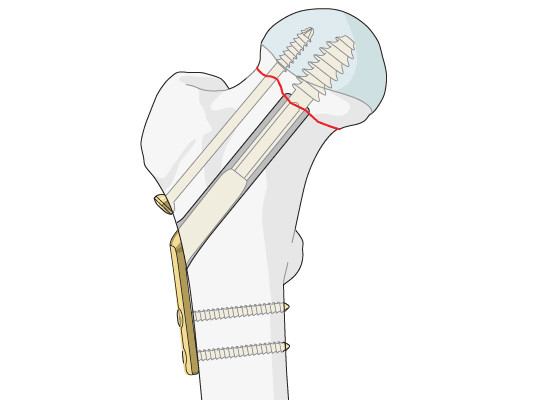

Trauma implant Cannulated Screw orthopedic implant,Cannulated Titanium Alloy Bone locking Screws,Medical Bone Screws

Features

1.Excellent design

2.Corrosion resistant

3. Precision Engineered

4. Durable finish

5. Easy to use

6. Entirely support bones

Durable 4.0 Mm Cannulated Screw Corrosion Resistant 20 - 68 Mm Length Images |